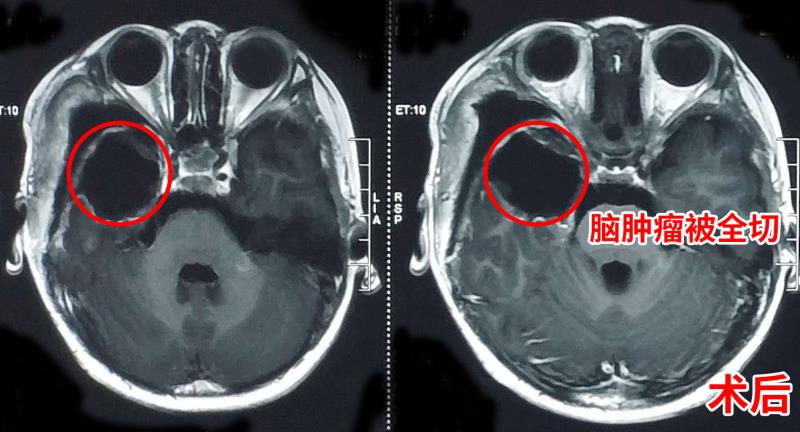

经过术前的病例讨论,完善术前相关检查,杰杰被推进手术室,孙玉明等神外三病区团队为杰杰实施了开颅肿瘤切除术,术中完好保护了重要的血管和神经以及相邻脑组织,肿瘤被全切除。术后,杰杰恢复良好,在病房和妈妈有说有笑,互动良好,让家人揪心的癫痫也没有再次发作。

孙玉明介绍,病理报告显示杰杰的脑肿瘤为多形性黄色星形细胞瘤,属于WHO 2级胶质瘤,比较罕见。目前儿童脑肿瘤在小儿肿瘤中的发病率仅次于白血病,是发病率较高的实体肿瘤。从2015年开始,儿童脑肿瘤的致死率已超过白血病。除胶质瘤外,常见的儿童脑肿瘤还有颅咽管瘤、生殖细胞肿瘤和室管膜瘤等。脑肿瘤好发于2个年龄阶段,第一高峰是在学龄前2-6岁,第二高峰是在青春期10-18岁。